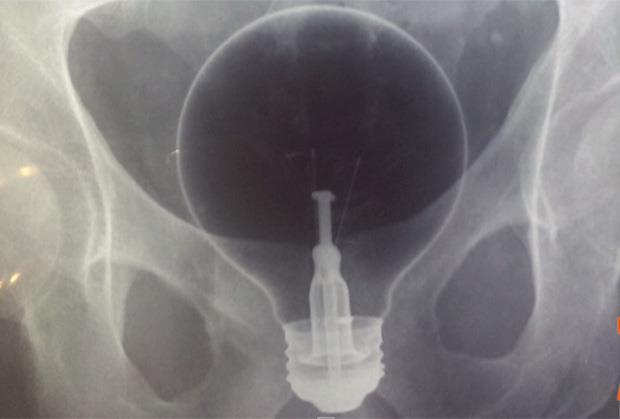

(VIDEO) BIZARNI SEKS: Vibrator zaglavila u bešici!